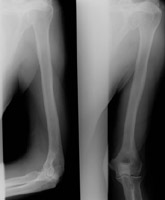

- Click on the image for a larger versionBAP and lateral radiographs of the humerus. One year prior, the lytic lesion is not apparent.

- Click on the image for a larger versionCAP radiograph of the humerus. A similar fracture of the humerus is apparent. Notice that there is no destructive process. This patient was in an automobile accident.